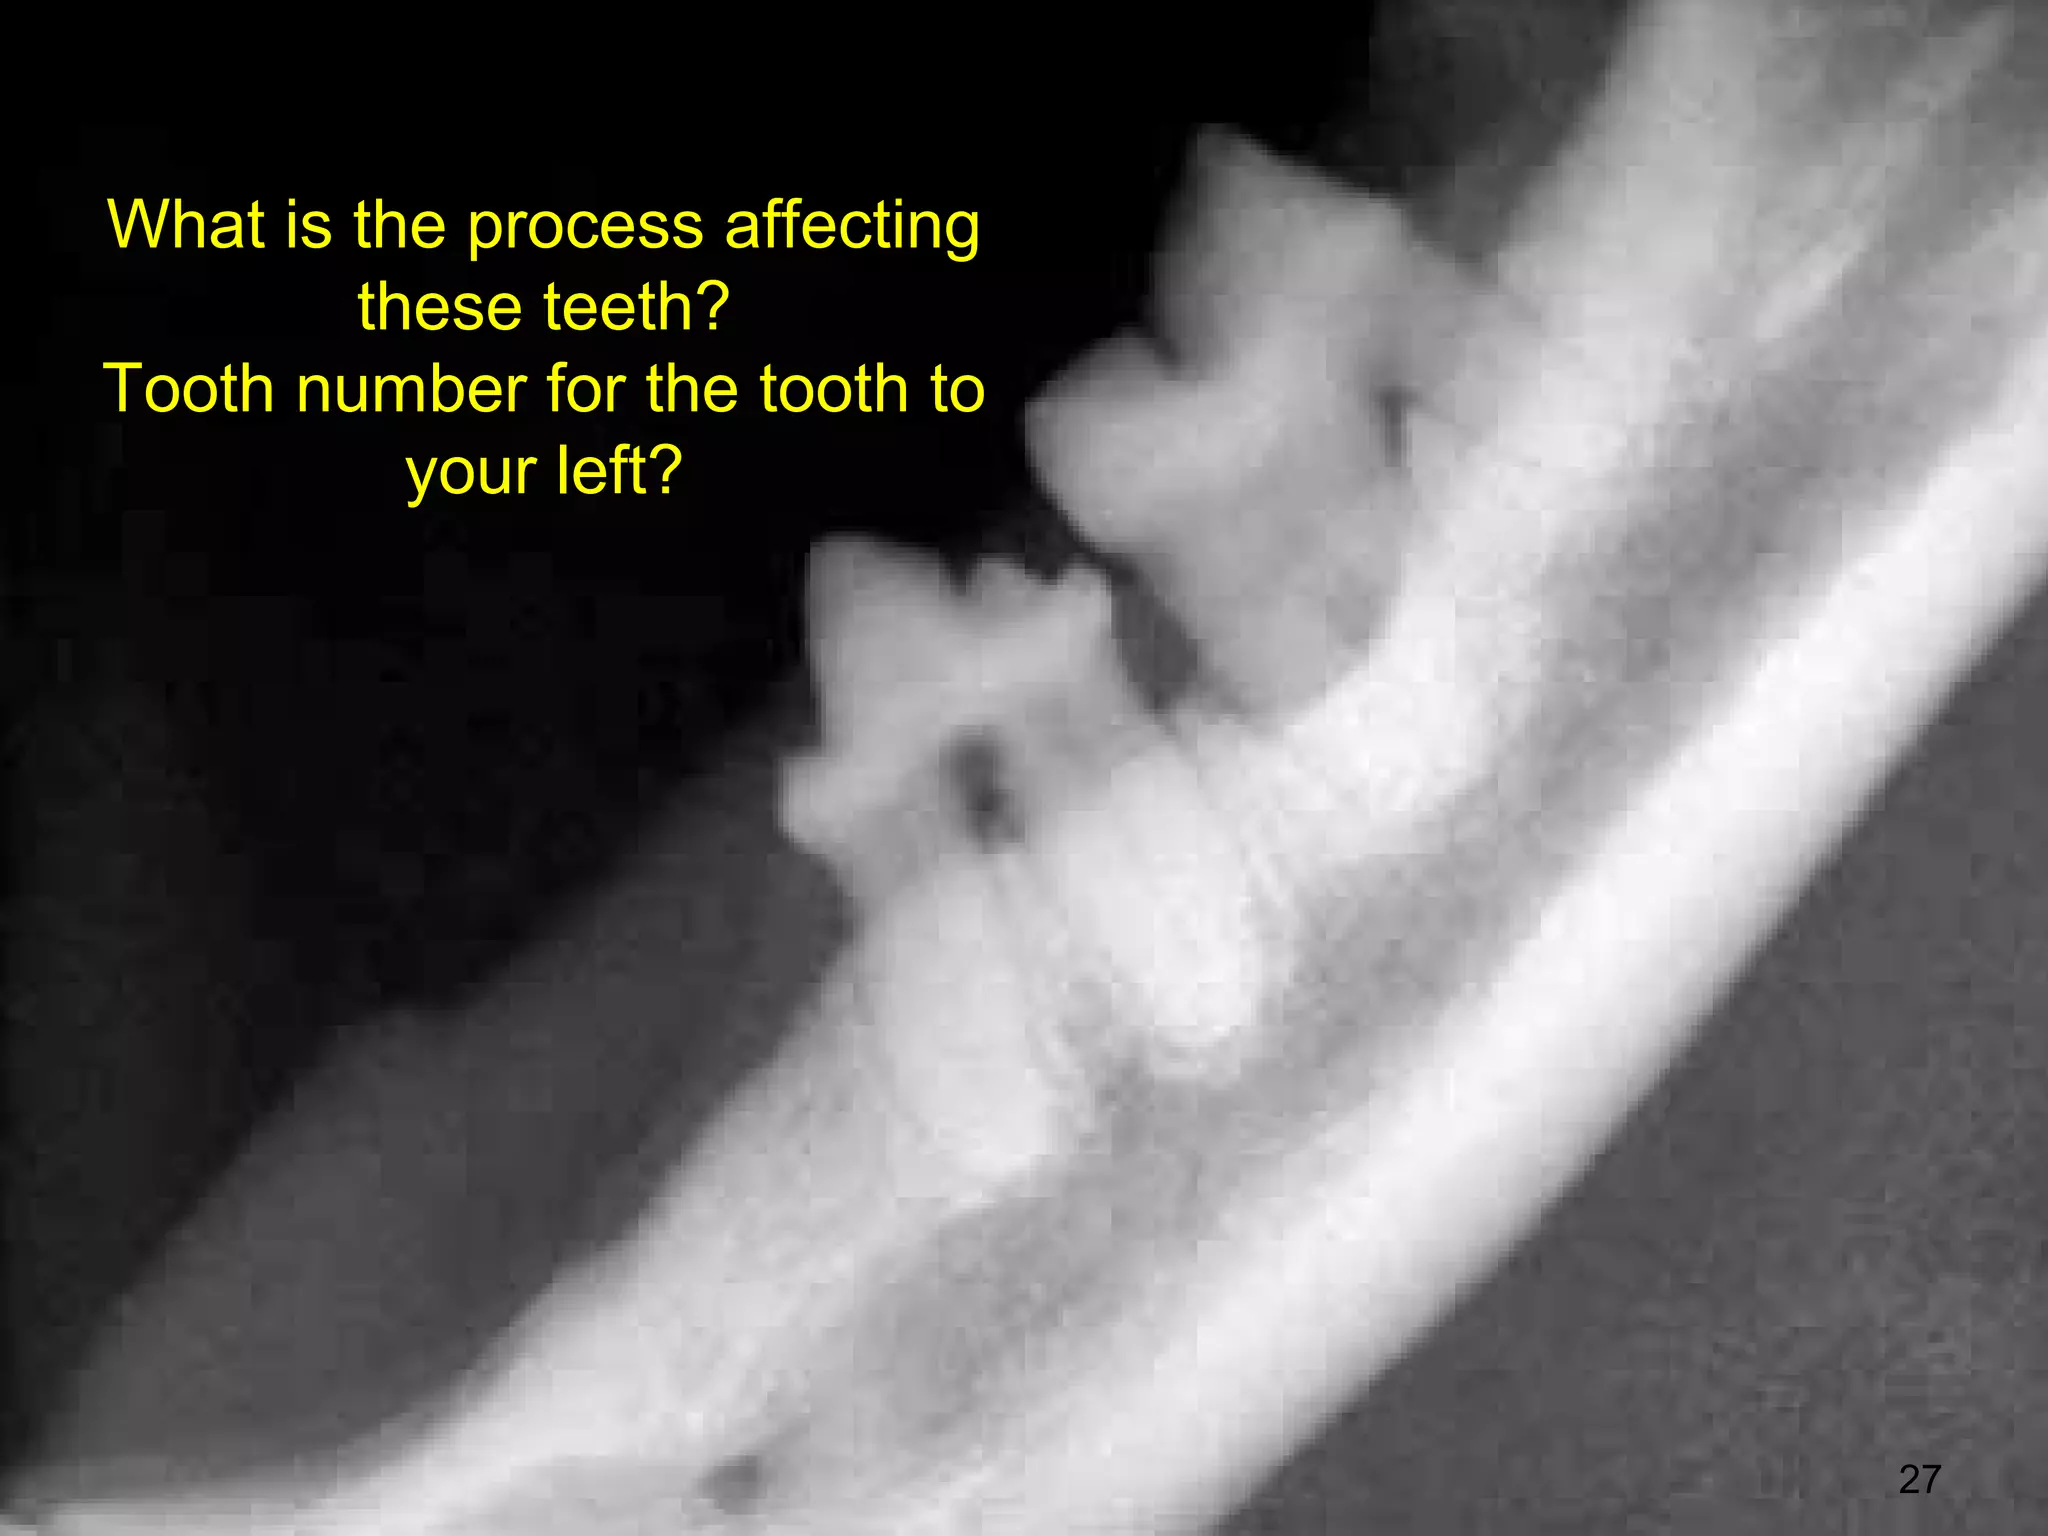

What is the process affecting

these teeth?

Tooth number for the tooth to

your left?

• 27.

What is theprocess affecting these teeth? Tooth number for the tooth to your left? 27